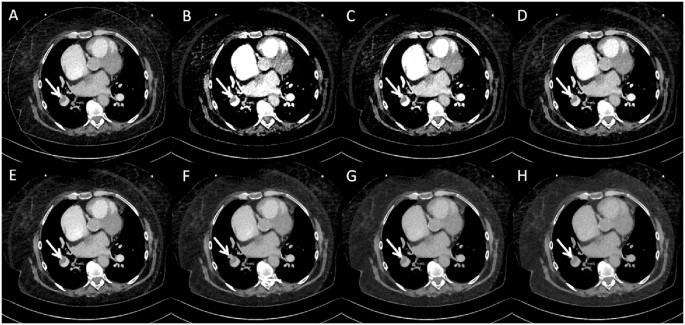

73-year-old woman with a peripheral pulmonary embolism (white arrows). Axial slices of main pulmonary arteries of a low contrast media dual-energy CTPA: (A) mixed 0.8-weighted virtual polyenergetic spectral (VPS) image, and virtual monoenergetic spectral (VMS) images at a level of 40 keV (B), 50 keV (C), 60 keV (D), 70 keV (E), 80 keV (F), 90 keV (G) and 100 keV (H).

No differences regarding background noise could be observed between the three protocols (standard CTPA 12.1 ± 2.1 HU vs. standard DE CTPA 10.4 ± 1.8 HU vs. low CM DE CTPA 14.3 ± 2.3 HU; for all p > 0.05). Vessel attenuation (enhancement) and image noise increased with decreasing energy levels for the 40–100 keV VMS datasets (compare Figs 2–4).

The 70 keV VMS dataset for the main pulmonary arteries showed the highest SNR (standard DE CTPA: 23.0 ± 9.1 vs. low CM DE CTPA 17.9 ± 2.8; p < 0.0001). The 50 keV dataset showed the highest CNR for both DE CTPA protocols, with significantly higher values for the standard DE CTPA protocol (p < 0.0001). When compared to the standard CTPA protocol datasets, CNR was significantly higher for both DE CTPA protocol VMS datasets at 50 keV (both p < 0.0073).

For the peripheral pulmonary arteries, the 50 keV VMS dataset of the low CM DE CTPA protocol showed the highest SNR and the 70 keV dataset of the standard DE CTPA protocol (standard DE CTPA: 15.6 ± 6.2 and low CM DE CTPA 14.0 ± 6.1). The 40 keV dataset revealed the highest CNR for the low DE CTPA protocol (p > 0.05) and for the standard DE CTPA protocol both 40 and 50 keV revealed the highest CNR. Similarly, when comparing the standard protocol to the 40 and 50 keV VMS datasets, there was a significant increase in CNR for both DE CTPA protocols (both p < 0.0064).